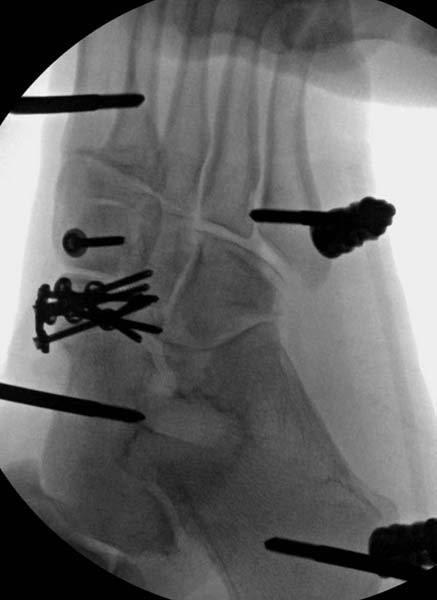

Через три дня повторная I&D, где через рану манипулировали дистальным фрагментом с установкой пары межфрагментарных шурупов. На рану вакуум и следующая обработка закончилась закрытием раны. Отек держался немного дольше, чем обычно.

После спадения отека вариантов фиксации много, включая мининвазивную технику, но данный случай закончили установкой простого аппарата Илизарова.

Через три дня оперирована стопа и для нейтрализации сил колонн оставили наружный фиксатор.